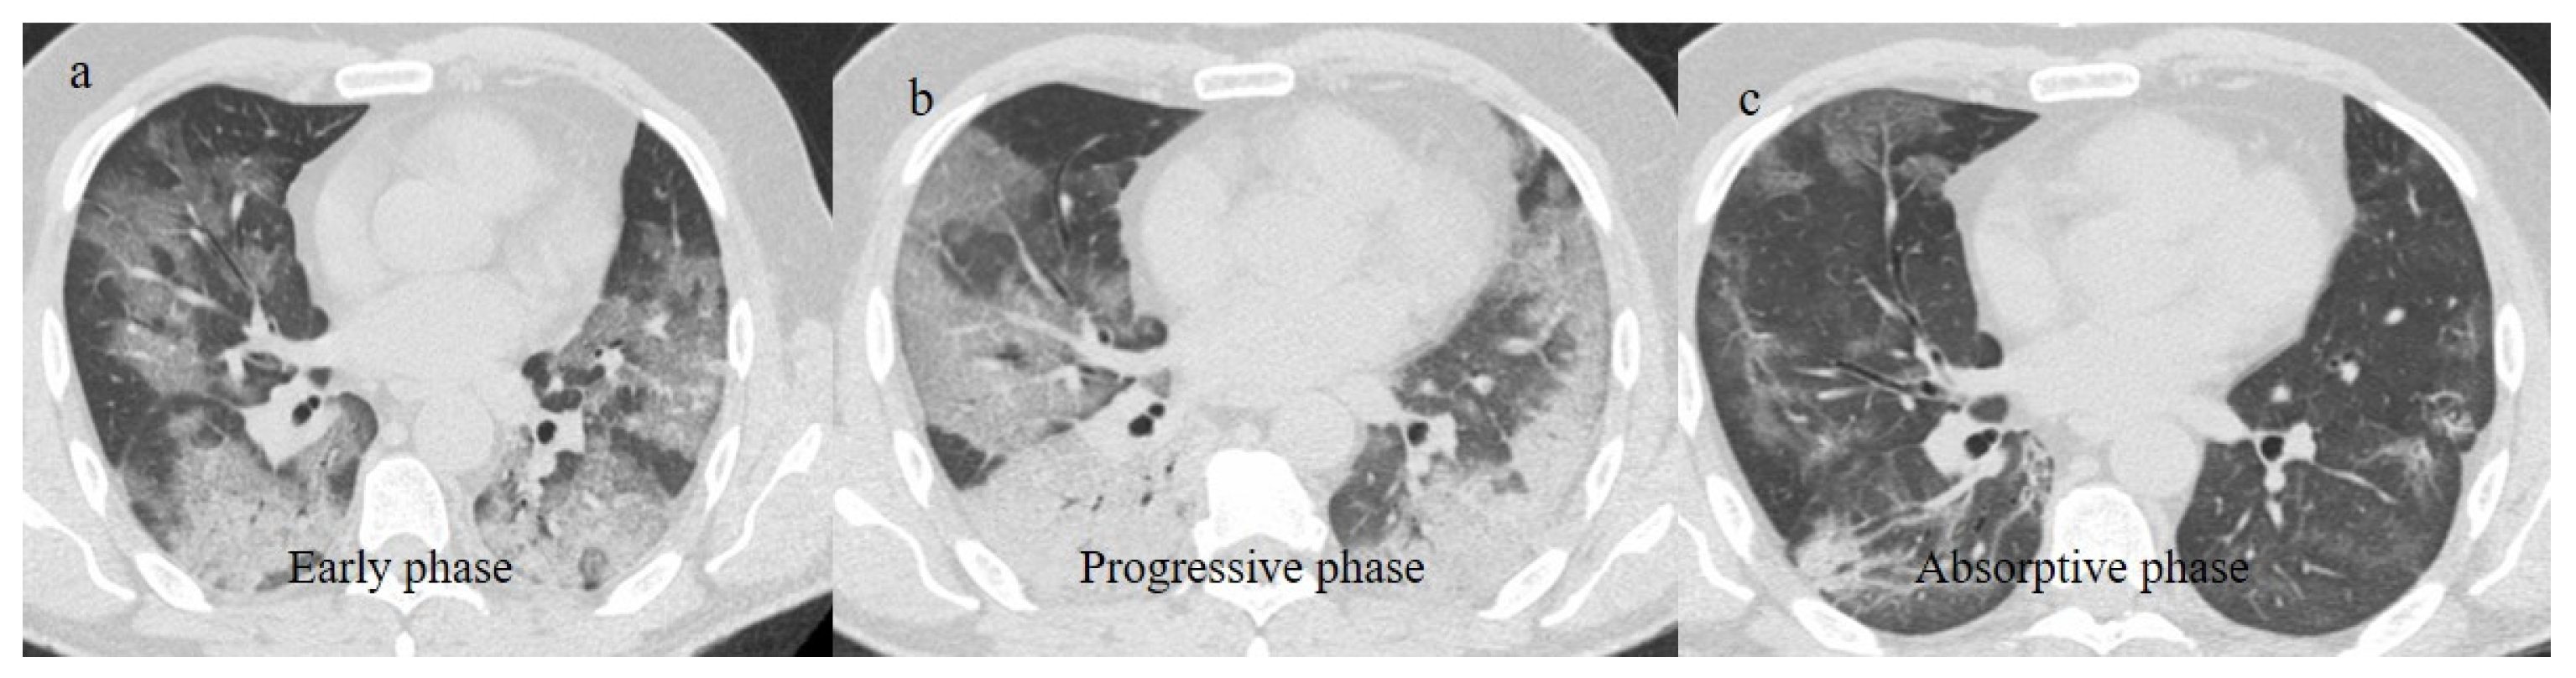

- Wang, Y.; Dong, C.; Hu, Y.; Li, C.; Ren, Q.; Zhang, X.; Shi, H.; Zhou, M. Temporal Changes of CT Findings in 90 Patients with COVID-19 Pneumonia: A Longitudinal Study. Radiology 2020, 296, E55–E64. [Google Scholar] [CrossRef]

- Hu, Q.; Guan, H.; Sun, Z.; Huang, L.; Chen, C.; Ai, T.; Pan, Y.; Xia, L. CT features and temporal lung changes in COVID-19 pneumonia in Wuhan, China. Eur. J. Radiol. 2020, 128, 109017. [Google Scholar] [CrossRef]